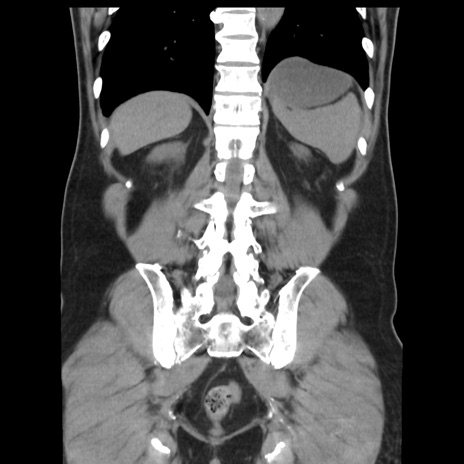

症例16(冠状断像)

【症例】 70歳代男性

【主訴】 腹痛、嘔吐

【現病歴】 約1ヶ月前より間欠的に腹痛と嘔吐あり、当院消化器内科を受診したところCTで多発する肝臓のLDAを指摘され、精査中であった。以降は消化器症状は安定していたが、2日前より嘔気と腹痛があり、同日より排便・排ガスが消失した。改善認めず、 本日、救急外来を受診した。

【既往歴】 大腸ポリープ切除後。

【身体所見】意識清明・会話良好、BT 36.3℃、BP 127/80mmHg、 P 80bpm、腹部:膨満あり、平坦・軟、上腹部正中および下腹部正中に圧痛あり、反跳痛なし、筋性防御なし。

【データ】WBC 7200、CRP 0.77